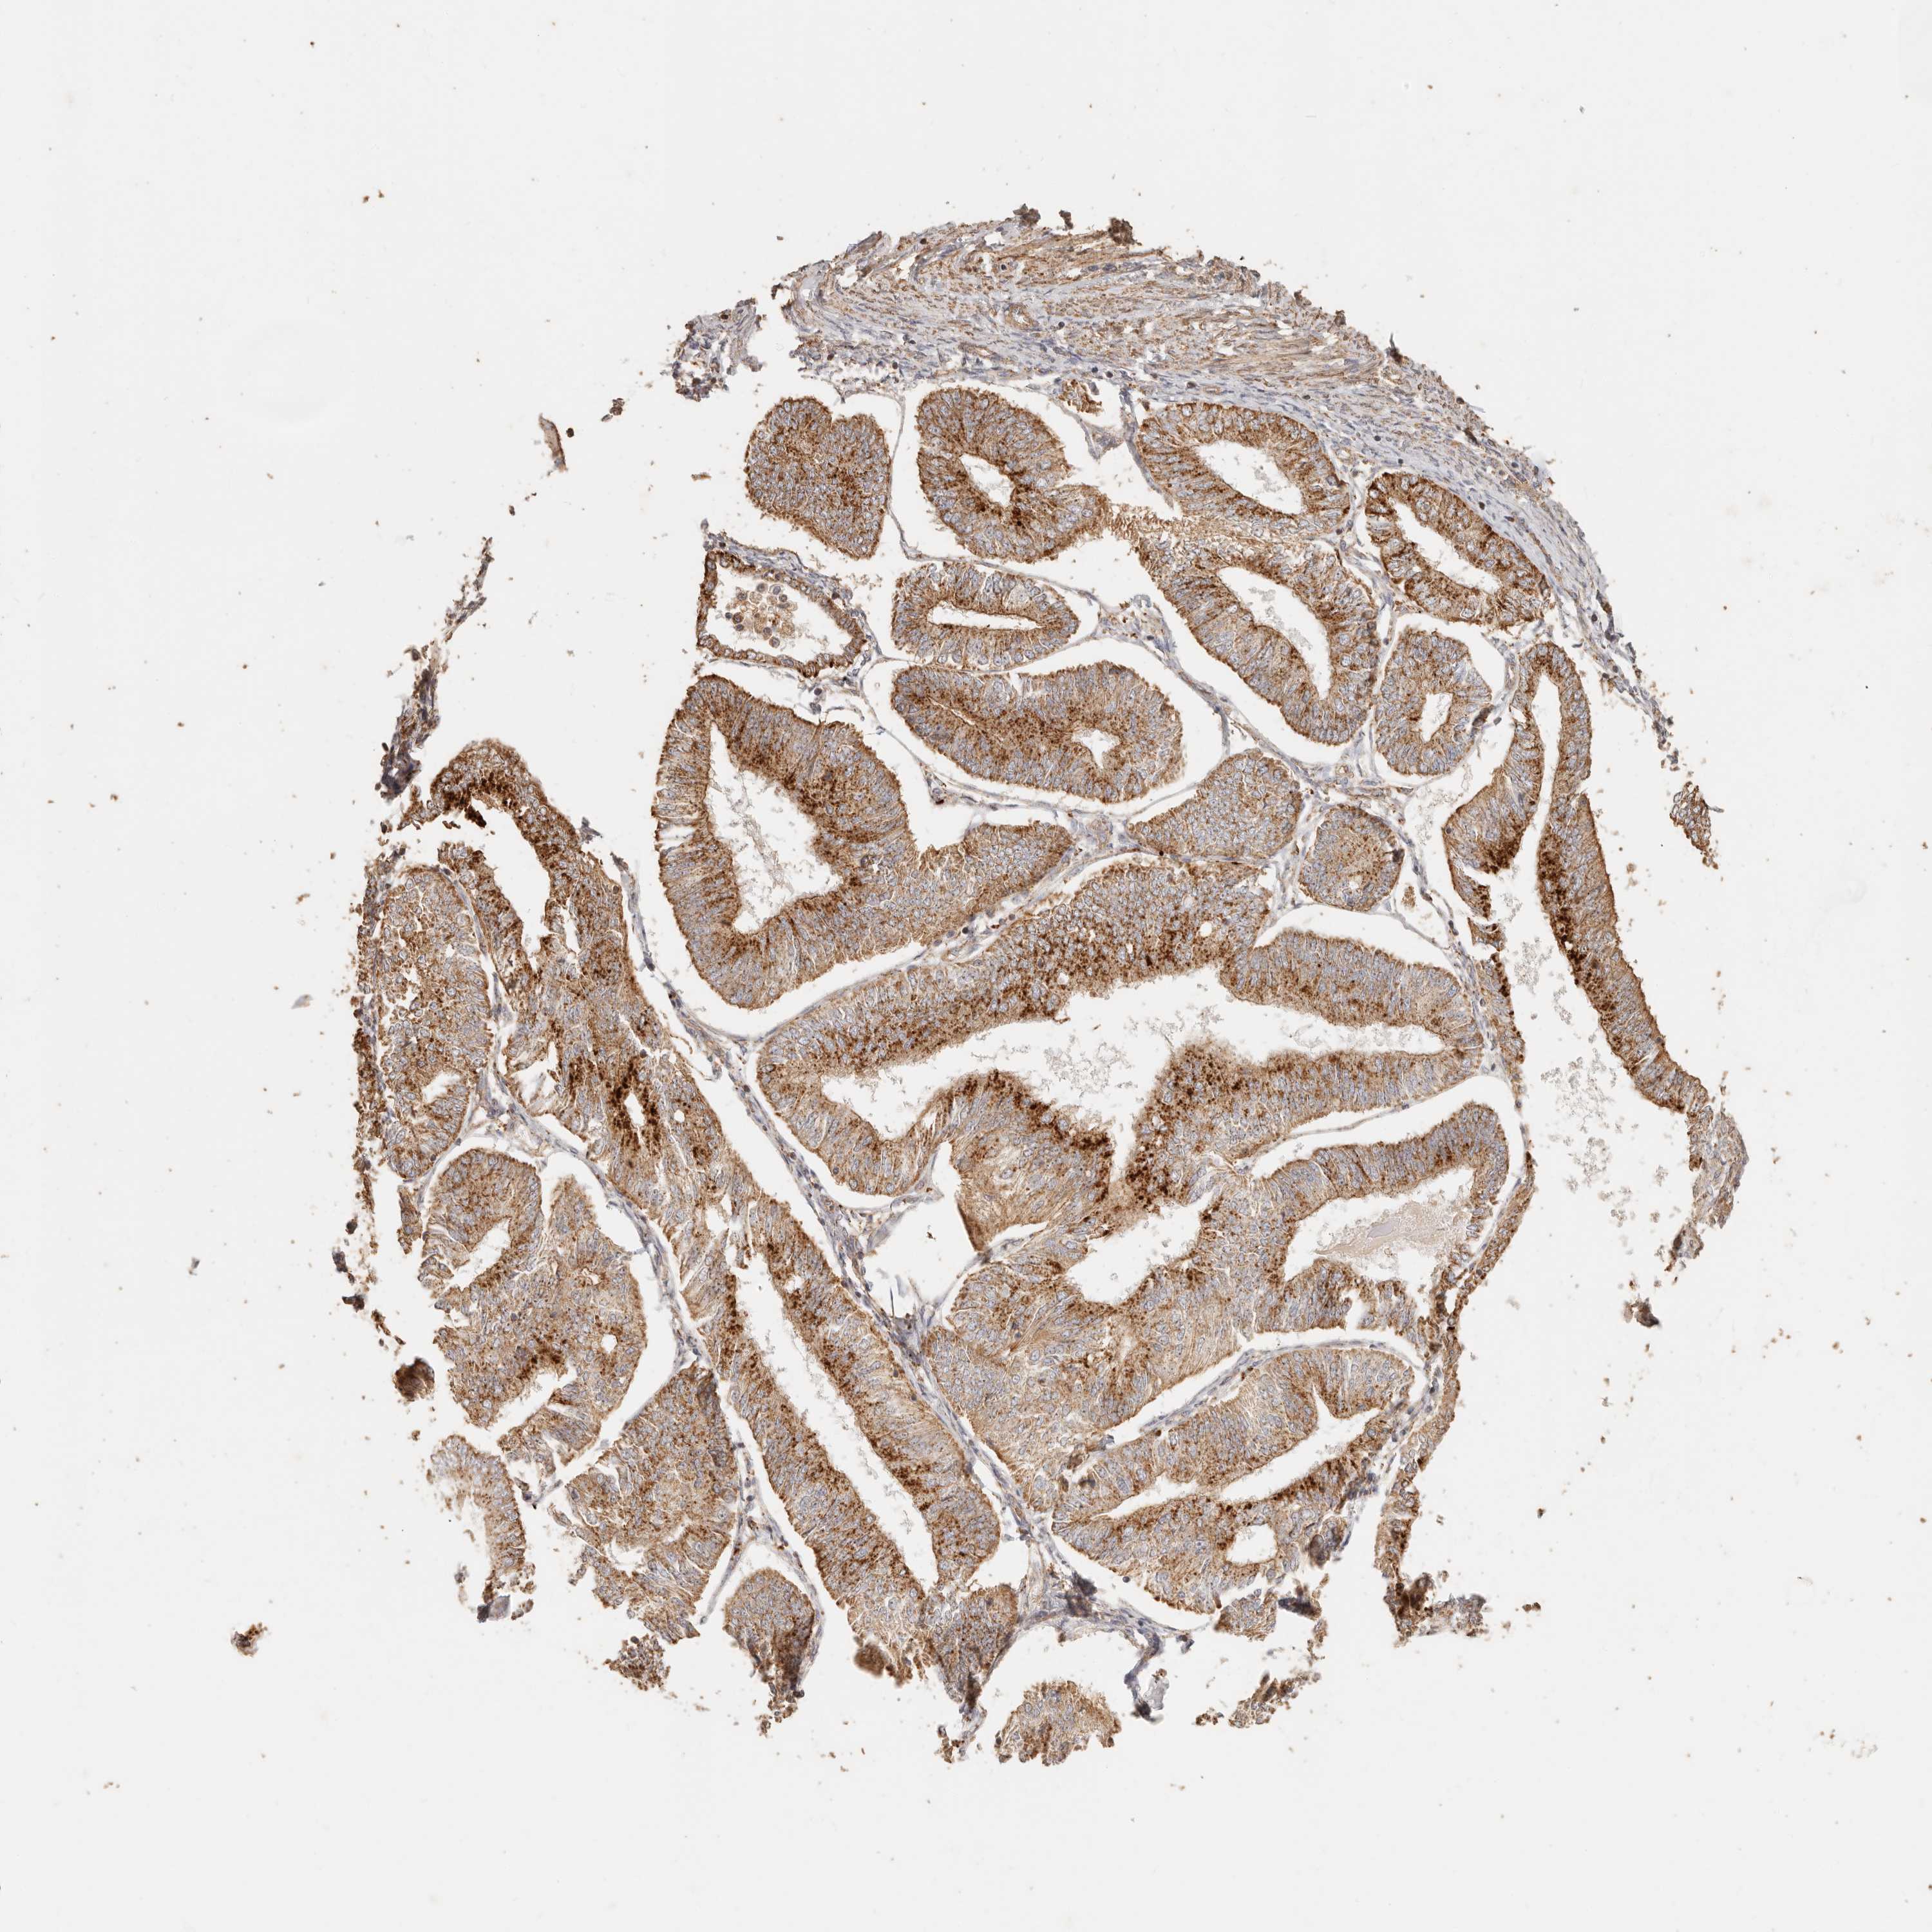

ENDOMETRIAL CANCER - Protein expressioni

A mouse-over function shows sample information and annotation data. Click on an image to view it in a full screen mode. Samples can be filtered based on level of antibody staining by selecting one or several of the following categories: high, medium, low and not detected. The assay and annotation is described here.

Note that samples used for immunohistochemistry by the Human Protein Atlas do not correspond to samples in the TCGA dataset.

Antibody stainingi

Antibody staining in the annotated cell types in the current human tissue is reported as not detected, low, medium, or high, based on conventional immunohistochemistry profiling in selected tissues. This score is based on the combination of the staining intensity and fraction of stained cells.

Each image is clickable and will lead to virtual microscopy that enables deeper exploration of all samples and also displays staining intensity scores, fraction scores and subcellular localization as well as patient and tissue information for each sample.

Antibody HPA004912

Antibody HPA013350

Antibody CAB012209

Staining

High

Medium

Low

Not detected

Intensity

Strong

Moderate

Weak

Negative

Quantity

>75%

75%-25%

<25%

None

Location

Nuclear

Cytoplasmic/membranous

Cytoplasmic/membranous,nuclear

Adenocarcinoma, NOS

Adenocarcinoma, metastatic, NOS